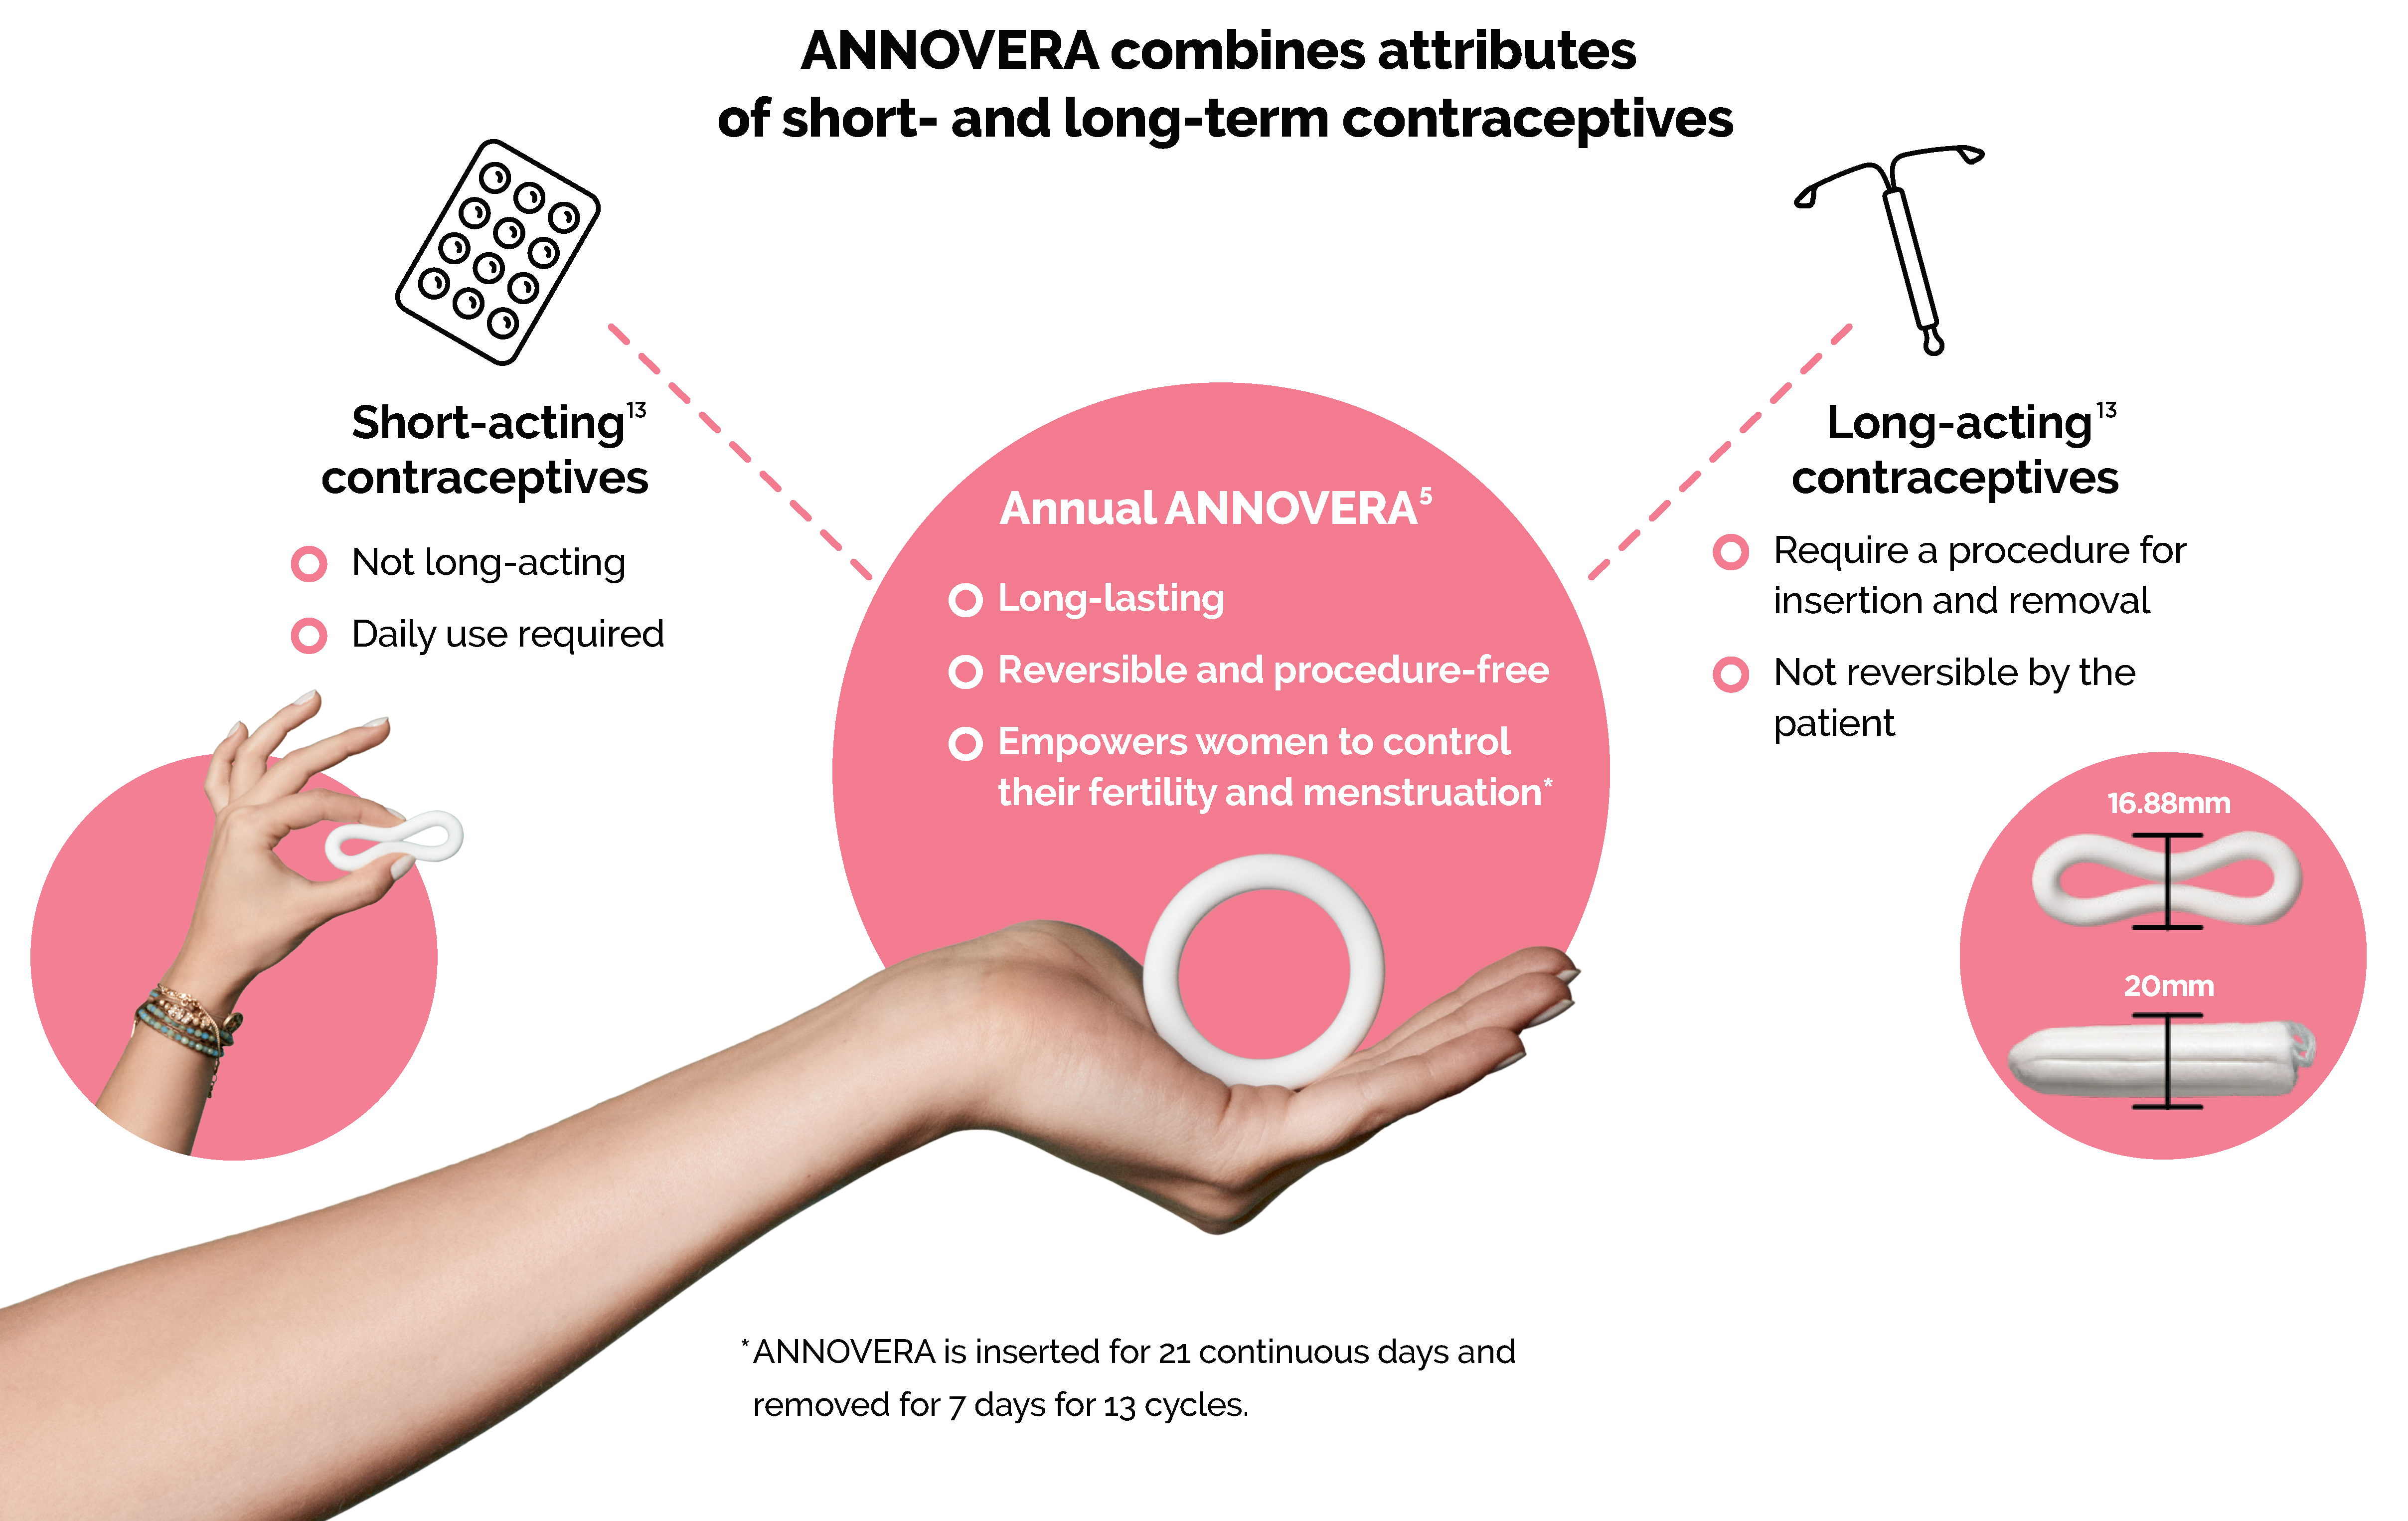

Annovera Ring Side Effects. After the 7 days are up insert Annovera again for the next 21 days and continue this process for up to 12 months. Nausea vomiting diarrhea stomach pain. If experienced these tend to have a Less Severe expression i. Headachemigraine nauseavomiting vaginal yeast infection candidiasis lowerupper abdominal pain painful periods vaginal discharge urinary tract infection breast paintenderness irregular vaginal bleeding diarrhea and genital itching.

Headache Nausea Breast tenderness Yeast infections Irregular bleeding Abdominal pain Genital itching During studies comparing the pill patch and ring researchers found that women who used the ring had more genital irritation and vaginal discharge than women who used the pill. Headache including migraine nauseavomiting vaginal yeast infection candidiasis lowerupper abdomen pain painful periods vaginal discharge urinary tract infection breast paintenderness irregular vaginal bleeding diarrhea genital itching USE ANNOVERA is a ring-shaped vaginal system with. Each of these side effects was experienced by fewer than 2 of the women participating. Call your doctor for medical advice about side effects. Get emergency medical help if you have signs of an allergic reaction. During the 7 days its removed youll get your period.

Annovera has similar side effects to the pill and NuvaRing because they use the same kind of hormones. Annovera has similar side effects to the pill and NuvaRing because they use the same kind of hormones. Annovera ring side effects. Its not listed on the brands list of side effects so I thought Id see if this has ever happened to other women or if I need to see a doctor. The use of a combination hormonal contraceptive CHC like ANNOVERA is associated with increased risks of several serious side effects including blood clots stroke or heart attack.

During a clinical trial of more than 2000 women using Annovera the side effects that caused women to stop using Annovera included irregular bleeding headaches vaginal discharge vaginal infections and nausea. Youd still need to remember to take out Annovera after 3 weeks of keeping it in place and then reinsert it after 1 week. Some less serious side effects include. ANNOVERA does not protect against HIV infection AIDS and other sexually transmitted infections. Allergic reactions such as skin rash or itching hives swelling of the lips mouth tongue or throat.

After the 7 days are up insert Annovera again for the next 21 days and continue this process for up to 12 months. Is anyone here on the Annovera ring. Uses How to use Side Effects Reviews Uncontrolled high blood pressure Heart problems Diabetes Increased risk of blood clots Undiagnosed abnormal uterine bleeding Potential hepatitis C drug combinations containing ombitasvir paritaprevir or ritonavir with or without. Annovera has similar side effects to the pill and NuvaRing because they use the same kind of hormones. Headachemigraine nauseavomiting vaginal yeast infection candidiasis lowerupper abdominal pain painful periods vaginal discharge urinary tract infection breast paintenderness irregular vaginal bleeding diarrhea and genital itching.

Headaches nausea abdominal pain increased period pain. Some less serious side effects include. Pain or burning when you urinate. Its not listed on the brands list of side effects so I thought Id see if this has ever happened to other women or if I need to see a doctor. Youd still need to remember to take out Annovera after 3 weeks of keeping it in place and then reinsert it after 1 week.